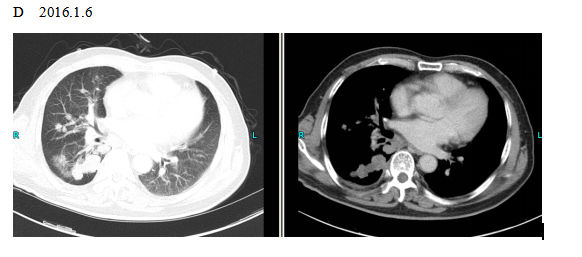

The patient checked for further treatment on November 23, 2015. A pre-chemotherapy assessment was made and the results showed multiple bone metastases and multiple enlarged lymph nodes in the left shoulder blade, the fourth lumbar, the right iliac bone and other locations. Performance status (PS) was only one point. Pemetrexed Disodium (500 mg/m2 d1) + Carboplatin (AUC 5 d1) + Bevacizumab (7.5 mg/Kg d1) was administered beginning November 26, 2015 for the chemotherapy treatment and supportive therapy was provided, such as, dehydration, reduction of intracranial pressure, promotion of bone repair, pain relief, and waist protection. After discharge, the coughing basically disappeared and the dizziness, backaches, and hemiparesthesia of the left side were significantly improved. Patient emotional state and sleep quality was significantly improved. It was basically normal after a routine blood examination. A second chemotherapy treatment was successfully completed on December 18 (the program is idem). The patient returned to the hospital on January 6, 2016 and was proposed for a third chemotherapy. The pre-chemotherapy assessment showed that the measurable, targeted right lung lesion had decreased (3.2 mm, with a rate of decrease 44.8 %) (Fig. 1D). Lymphangitis carcinomatosa was significantly decreased and right frontal nodulus lesions were reduced significantly (Fig. 2C). No new lesions were found. Efficacy was assessed as partial relief (PR). A third and fourth chemotherapies were completed on January 9 and January 30, 2016. Efficacy was re-assessed as PR (Fig. 1E) with lung CT review as an outpatient on February 11. Since then, the patient had been subjected to a combined administration program of pemetrexed disodium (500 mg/m2 d1) + bevacizumab (7.5 mg/Kg d1) for continued chemotherapy. A lung CT and a cranial MRI were peformed on April 16. The results showed that the control of lung lesions and intracranial lesions were basically the same as before (Fig.1F and Fig. 2D). The patient had no cough, backaches, or hemiparesthesia and the quality life significantly improved. PS was decreased to zero.